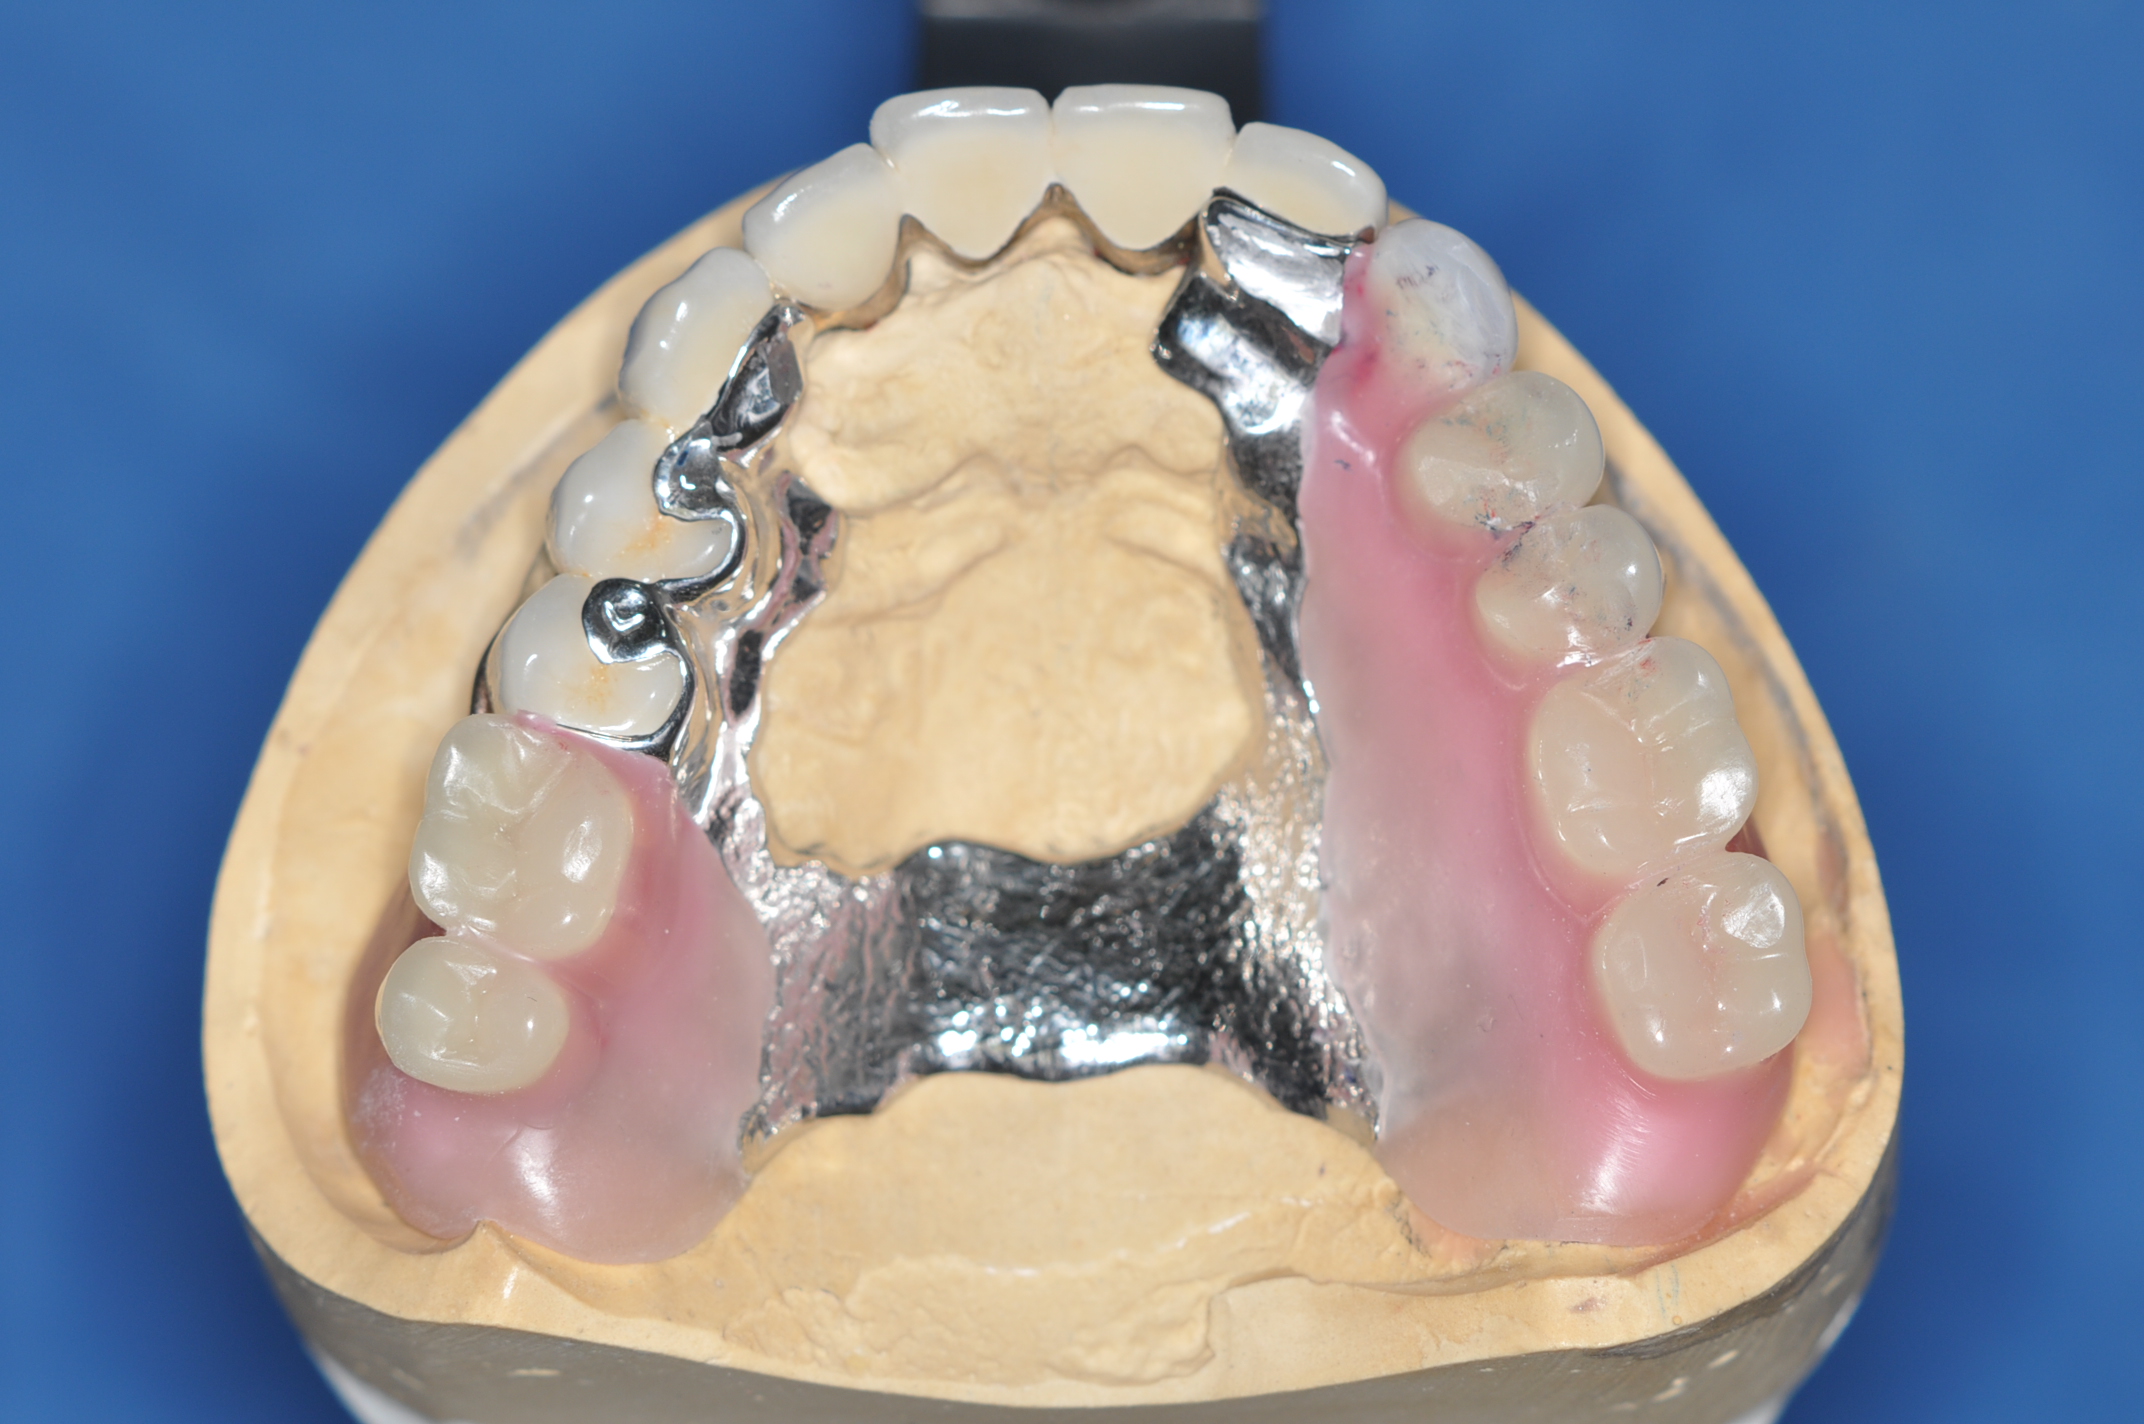

50代女性 部分義歯で対応した重度歯周病症例

娘さんがHPで安藤歯科を探していただいたそうです。義歯が入っているように見えない事が治療条件でした。

試適時の咬みわせチェックの写真です。装着時も咬合器にリマウントしてチェックします。

治療内容

歯周基本治療

歯周外科

抜歯

補綴治療

使用装置

仮義歯

抜歯部位

FDI表記 23 25 26 35 37 42 44 45 47